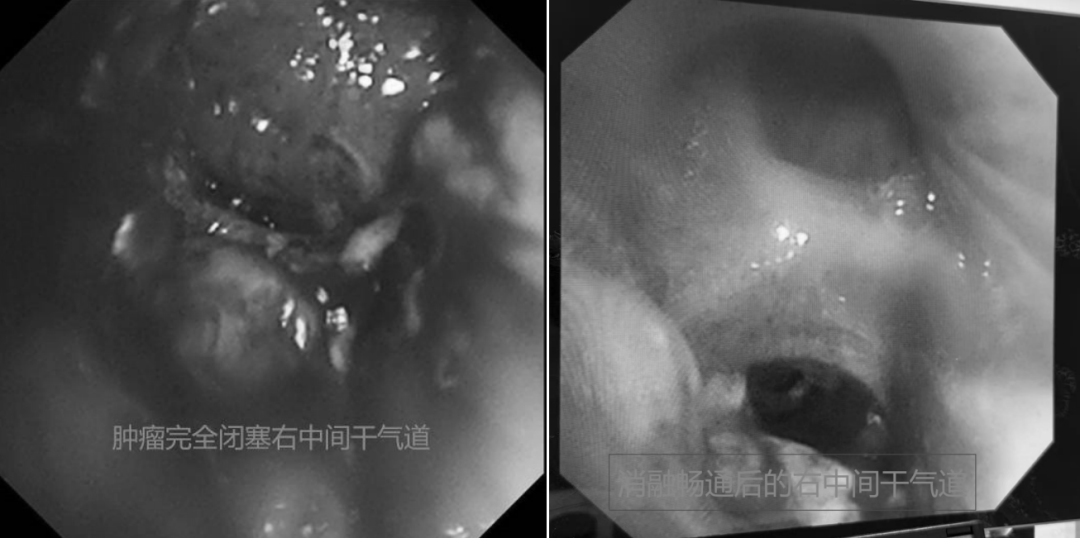

随后,徐涛副主任带领团队为患者进行气管插管下气管镜检查,进一步明确呼吸窘迫气道原因。检查发现,患者隆突处肿物增生及右中间干肿物完全闭塞远端气道,导致主气道狭窄闭塞、右下肺不张合并通气障碍,立即给予气道内肿物内镜下消融清理以解除气道梗阻、复张肺部。重症医学科病区主任于帮旭及平度肿瘤科副主任肖文静针对患者的复杂危重病情,制定个体化治疗方案,通过机械通气、抗感染、激素抗炎、改善心肺功能、化痰保肝、营养支持等综合支持治疗,全力改善患者病情。经过多学科团队的精细化综合治疗,患者病情显著好转,已于近日康复出院。

治疗前 治疗后